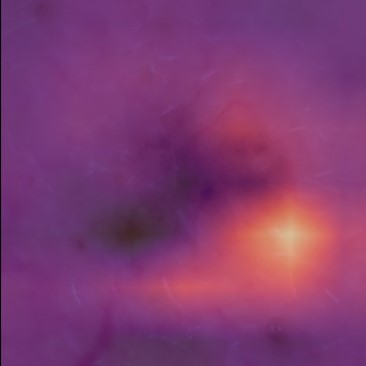

State-of-the-art deep learning approaches for skin lesion recognition often require pretraining on larger and more varied datasets, to overcome the generalization limitations derived from the reduced size of the skin lesion imaging datasets. ImageNet is often used as the pretraining dataset, but its transferring potential is hindered by the domain gap between the source dataset and the target dermatoscopic scenario. In this work, we introduce a novel pretraining approach that sequentially trains a series of Self-Supervised Learning pretext tasks and only requires the unlabeled skin lesion imaging data. We present a simple methodology to establish an ordering that defines a pretext task curriculum. For the multi-class skin lesion classification problem, and ISIC-2019 dataset, we provide experimental evidence showing that: i) a model pretrained by a curriculum of pretext tasks outperforms models pretrained by individual pretext tasks, and ii) a model pretrained by the optimal pretext task curriculum outperforms a model pretrained on ImageNet. We demonstrate that this performance gain is related to the fact that the curriculum of pretext tasks better focuses the attention of the final model on the skin lesion. Beyond performance improvement, this strategy allows for a large reduction in the training time with respect to ImageNet pretraining, which is especially advantageous for network architectures tailored for a specific problem.

翻译:在皮肤损伤识别方面,最先进的深层学习方法往往要求就更大规模、更多样化的数据集进行预先培训,以克服因皮肤损伤成像数据集规模缩小而产生的一般限制。图像网通常用作预培训数据集,但其转移潜力受到源数据集和目标皮肤科情景之间领域差距的阻碍。在这项工作中,我们采用新的预培训方法,按顺序培训一系列自我监视学习的借口任务,只要求不贴标签的皮肤损伤成像数据。我们提出了一个简单的方法,以建立一个命令来界定一个托辞任务课程。对于多级皮肤损伤分类问题和ISIC-2019数据集,我们提供了实验性证据,表明:一) 由一个托辞任务课程比个人托辞任务预先训练的模式更优于模型,这在图像网上培训模型比模型先培训更优于模型。我们证明,这一业绩收益与以下事实有关:一个更突出托辞任务的重点,即界定一个托辞任务课程,确定一个托辞任务大纲。对于多级皮肤损伤分类问题,以及ISIC-2019数据集,我们提供了实验性地证明:一模型预设的模型的模型预设型模型预训练模型,使得最终的升级模型能够改进。